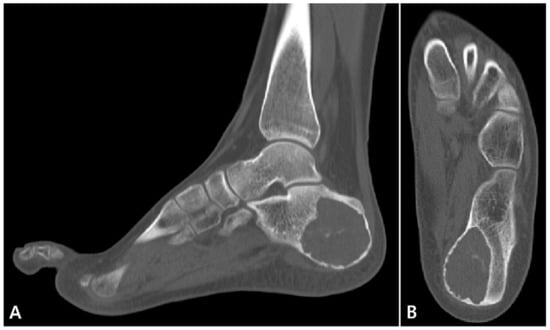

2. Case Presentation

2.1. Preoperative Evaluation